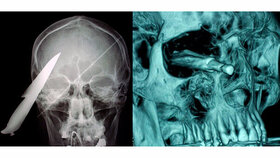

Durch den Zusammenstoß wurde ihr Unterkiefer gespalten und die gesamte linke untere Gesichtshälfte bis zum Gelenk verschoben. Dabei rissen nach Auskunft ihres Arztes Dr. Ricardo Mohammed-Ali, Facharzt für Gesichtsrekonstruktion, auch der Nervus mentalis und ein weiterer Seitenarm des Nervus alveolaris inferior. Bei Einlieferung in das Kinderkrankenhaus Sheffield des Nationalen Gesundheitsdienstes (NHS) wurde der beschädigte Gesichtsteil nur noch von einem etwa ein Zentimeter breiten Hautstreifen gehalten.

Emily wurde mit einem Rettungswagen in die Notaufnahme nach Sheffield gebracht. Nach der Untersuchung wurde sie sofort operiert. Die Operation dauerte nach Auskunft des Krankenhauses fast fünf Stunden. Insgesamt drei Titanplatten wurden in den Kiefer gesetzt, ein Knochen entfernt und abschließend die Wunde mit 160 Nadelstichen genäht. Bis auf einen Zahn konnten alle Zähne erhalten werden.